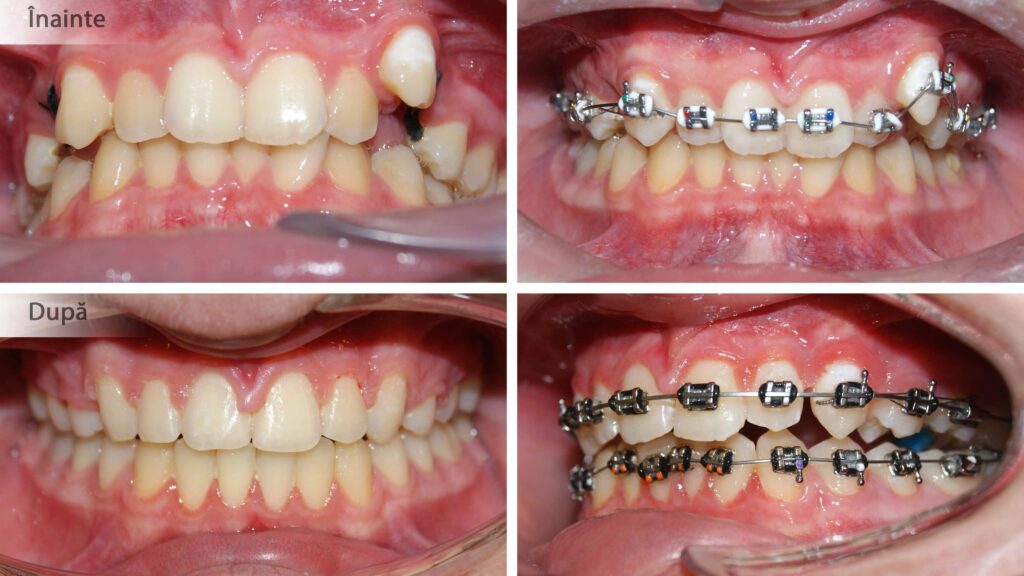

Crearea spațiului pentru alinierea dinților și pentru corectarea mușcăturii încrucișate.

Corectarea angulațiilor dentare și a mușcăturii

Îndreptarea axelor dentare are un efect semnificativ atât asupra dinților cât și asupra țesuturilor de susținere